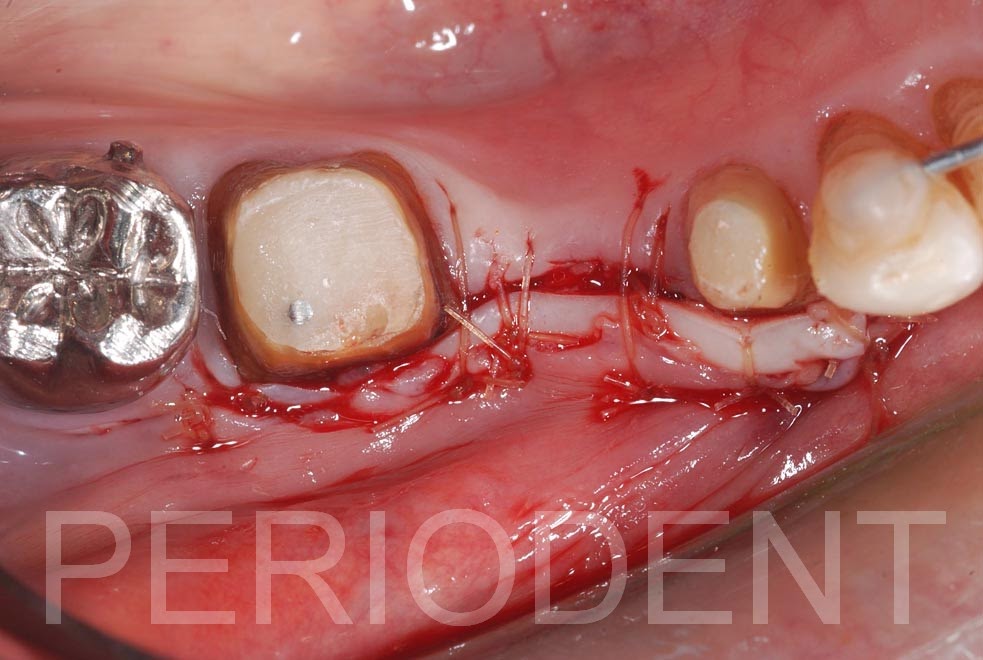

患者右下牙橋因為假牙不密合,根管充填不全而決定拆除假牙重做

因為角化牙齦不足,繫帶牽引及第一大臼齒牙齦線不良,

所以進行角化牙齦移植及同時牙根覆蓋